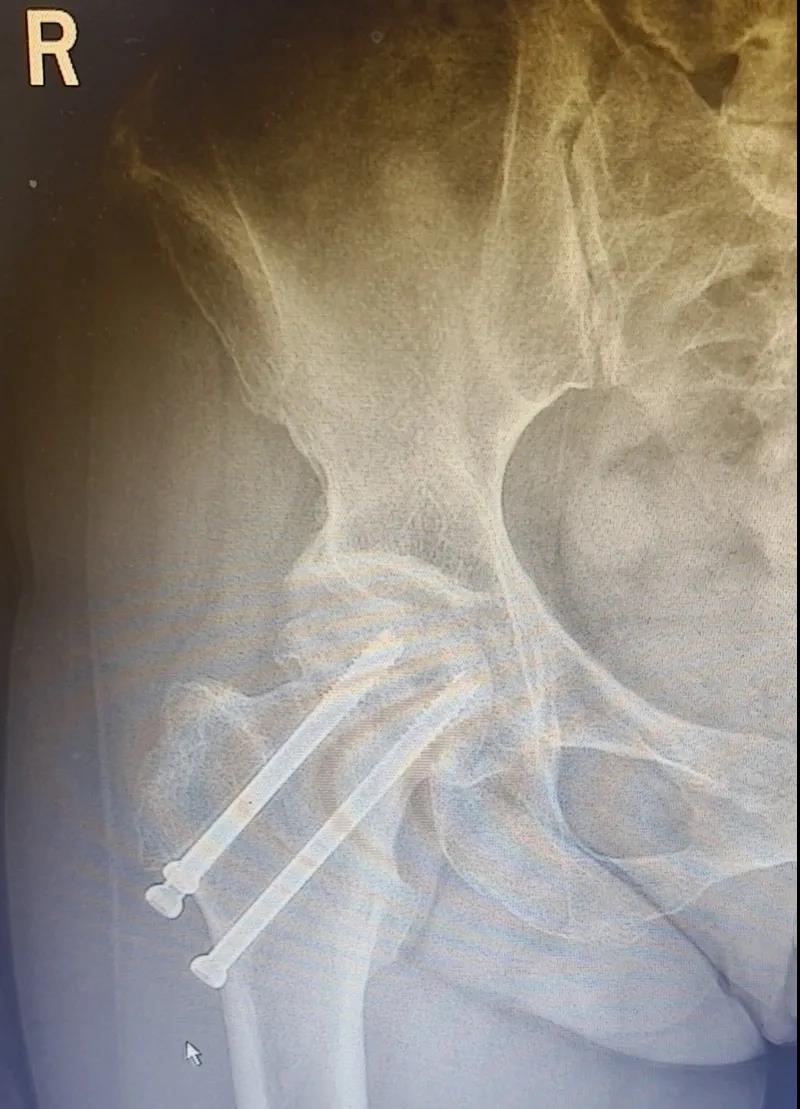

據(jù)李女士自述,自己于3年前因外傷致右股骨頸骨折,當(dāng)時(shí)在其他醫(yī)院做了右股骨頸骨折閉合復(fù)位螺釘內(nèi)固定術(shù),一年后右髖出現(xiàn)疼痛并逐漸加重,且休息不能緩解,行走時(shí)就像有座山壓身上一樣。

結(jié)合病癥表現(xiàn)及影像顯示,李女士被診斷為“右股骨頸骨折術(shù)后股骨頭壞死”,需要盡快做手術(shù)。

(△術(shù)前影像,右股骨頸骨折內(nèi)固定術(shù)后股骨頭壞死)

(△做完“右股骨頸全髖關(guān)節(jié)置換術(shù)”后的影像)